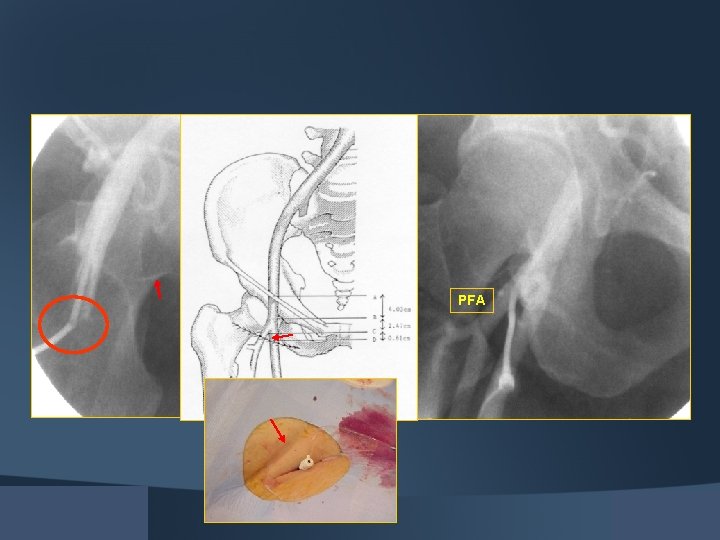

PFA

TYPE 1 Centerline Target Zone